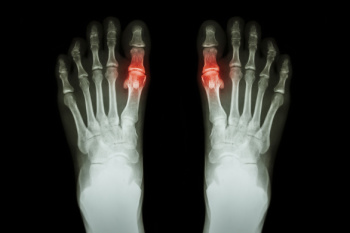

The Four Stages of Gout

Gout is a form of inflammatory arthritis caused by the buildup of uric acid crystals in the joints, often the big toe. It typically develops in four stages, each with distinct characteristics. The first stage, asymptomatic hyperuricemia, occurs when uric acid levels in the blood are high but no symptoms appear. Over time, if untreated, it can progress to the second stage, which is the acute gout attack. This stage is marked by sudden, severe pain, redness, and swelling, usually in the big toe. After the attack subsides, the condition may enter the third stage, intercritical gout, where symptoms do not occur but uric acid levels remain elevated. The final stage, chronic gout, can develop after repeated attacks, leading to joint damage and the formation of tophi, which are lumps of uric acid crystals under the skin. Common causes of gout include genetics, obesity, a diet high in purines, and certain medical conditions that affect uric acid processing. If you have severe pain in your big toe, it may indicate gout has developed, and it is suggested that you consult a podiatrist who can help you to manage this painful condition.

Gout is a form of arthritis that is characterized by sudden, severe attacks of pain, redness, and tenderness in the joints. The condition usually affects the joint at the base of the big toe. A gout attack can occur at any random time, such as the middle of the night while you are asleep.

Symptoms

- Intense Joint Pain - Usually around the large joint of your big toe, and it most severe within the first four to twelve hours

- Lingering Discomfort - Joint discomfort may last from a few days to a few weeks

- Inflammation and Redness -Affected joints may become swollen, tender, warm and red

- Limited Range of Motion - May experience a decrease in joint mobility